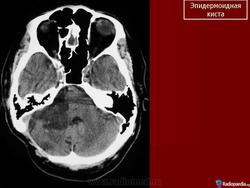

С 1985 по 2000 г.г. в НИИ нейрохирургии им. Н.Н. Бурденко обследовано и оперировано 78 больных с эпидермоидными кистами задней черепной ямки. Изучен клинический симптомокомплекс и КТ, МРТ картина эпидермоидных кист задней черепной ямки.

Качество оперативного лечения оценивалось изучением динамики неврологического статуса, данных КТ, МРТ, как до операции, так и после операции на разных его стадиях. Современные радиологические исследования и микрохирургическая техника полностью обеспечивает радикальное удаление эпидермоидных кист с хорошим после операционным результатом.

Эпидермоидная киста